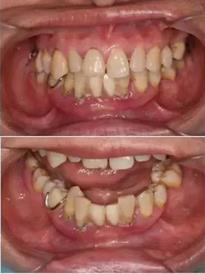

▲ 女性,42歲,牙周病,下前牙固定不良修復(fù)體,基牙炎癥、松動(dòng)。

初診時(shí)下前牙不良修復(fù)體

去除不良修復(fù)體后鄰牙松動(dòng)

拔牙后照片